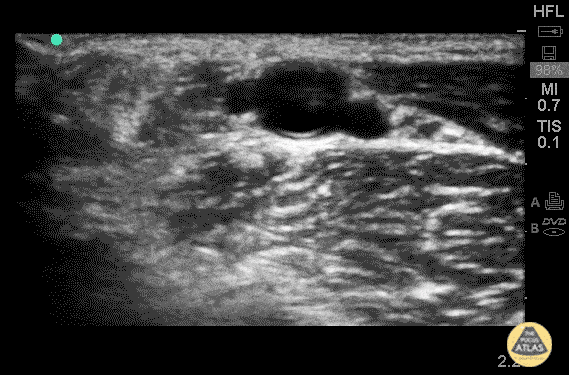

Vascular - Radial Artery Thrombus (Pre/Post TPA)

The images above are from a middle-aged woman who presented to the emergency room as a stroke code. She complained of paresthesias in her right arm and had decreased sensation to light touch. It was noted that this arm was colder than the left, so after she returned from head CT, POCUS was performed of her brachial artery. There is a non-compressible hyperechoic structure inside the brachialartery, consistent with the clinical picture of an arterial embolus. Given the urgency of stroke treatment, these images were obtained after the stroke team had administered tenecteplase. Vascular surgery consult was made aware of the findings and repeat images taken an hour after presentation and administration of tenecteplase were obtained at bedside with the vascular surgery consult. These images show near resolution of the embolus. Dr. Ben Kaufman